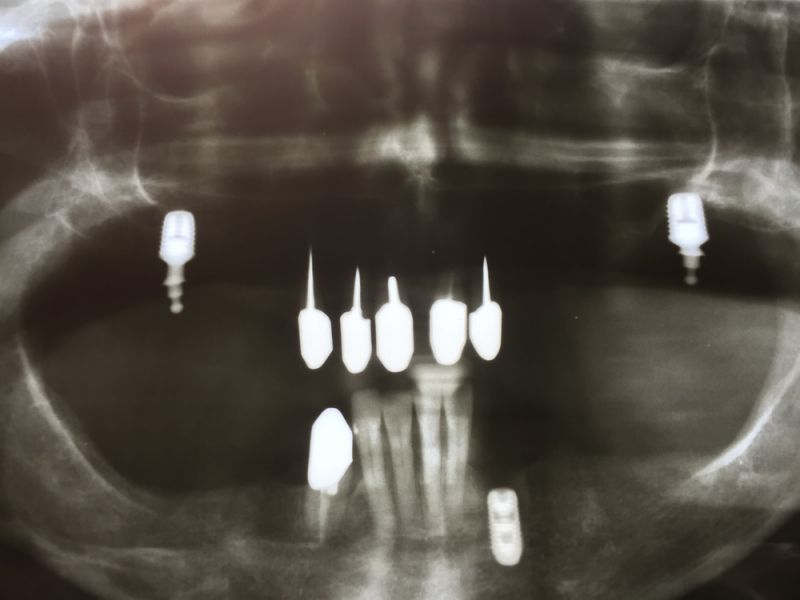

Rekonstruierte Kieler Patientin erhält ein Implantat

Nach der Entfernung des Zahnes 33 und entsprechender Abheilungsphase wurde heute ein Implantat inseriert. Nach Einheilung und Einbindung in die vorhandene Prothesenrekonstruktion soll nachfolgend dann Zahn 43 entfernt und ebenfalls durch ein Implantat ersetzt werden